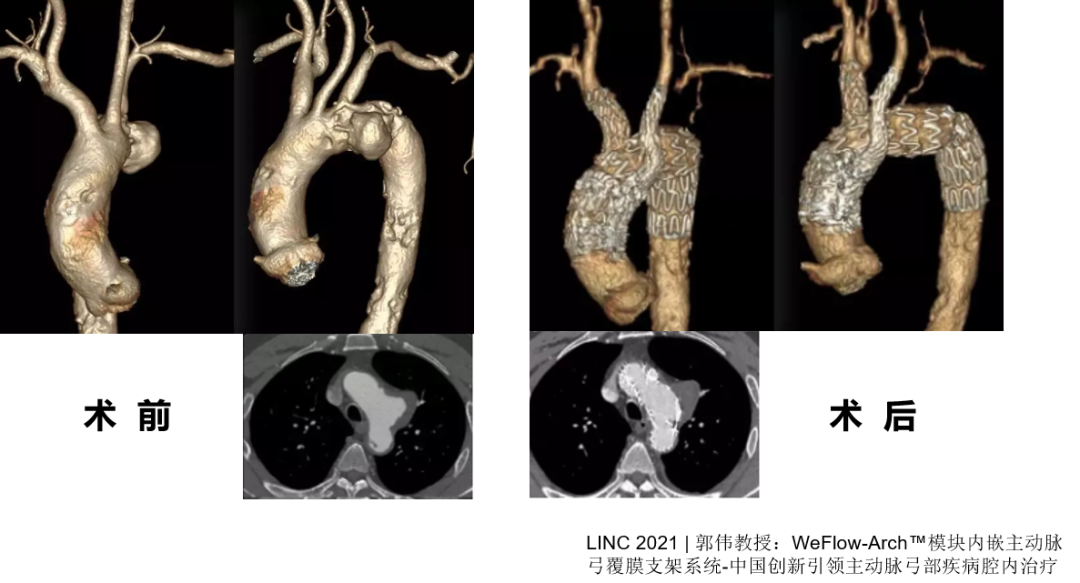

WeFlow-Arch™病例展示

★ 病例1:模块内嵌分支胸主动脉覆膜支架系统

★ 病例2:模块内嵌分支胸主动脉覆膜支架系统

术前

术后